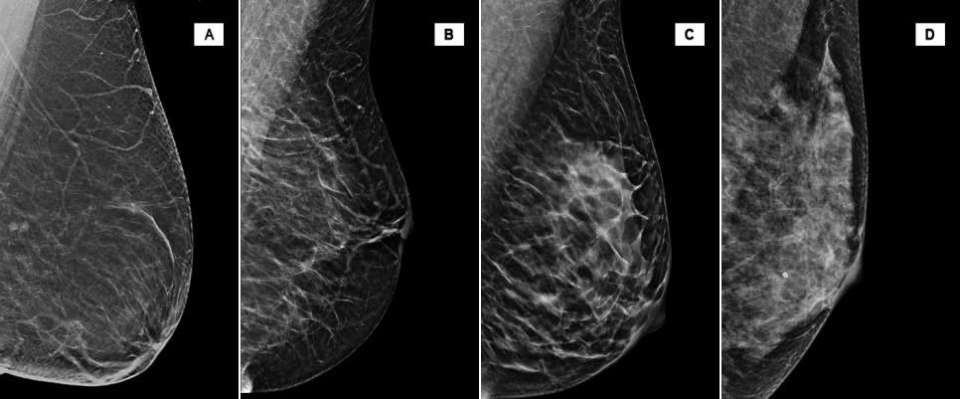

Breast Density

(A) The breasts are almost entirely fatty. (B) There are scattered areas of fibroglandular density. (C) The breasts are heterogeneously dense, which may obscure small masses. (D) The breasts are extremely dense, which lowers the sensitivity on mammography.

Current literature reports the proportion of the screening population in each category as 10% in Category A, 40% in Category B, 40% in Category C, and 10% in Category D. Therefore, approximately 50% of screening population has dense breast tissue, as defined by BI-RADS [1].